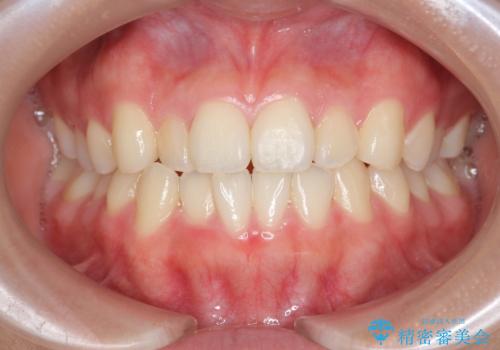

[ マウスピース矯正 ] 前歯のねじれを治したい

![[ マウスピース矯正 ] 前歯のねじれを治したいの症例 治療前](https://seimitsushinbi.jp/wp/wp-content/uploads/2022/01/IMG_1344-500x350.jpg?v=1641871025)